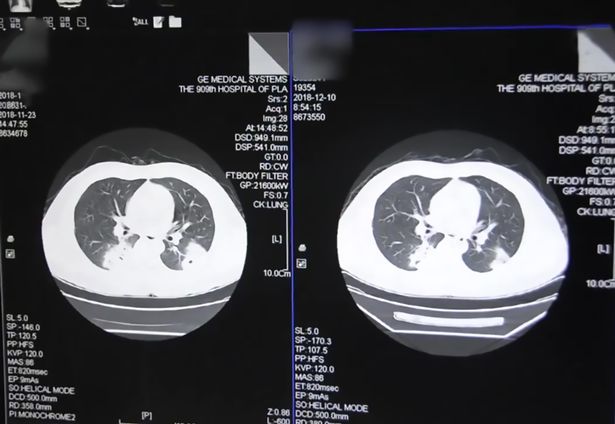

그러던 어느날 그는 극심한 가슴 통증을 느끼기 시작하다 결국 응급실에 실려가 치료를 받앗고 가슴 엑스레이 사진으로 그의 폐가 진균에 감염된 것을 확인할 수 있었다.

의료진은 그가 발 땀으로 인해 양말에 진균이 생겼으며 매일 양말 냄새를 맡은 행위로 인해 균이 폐 속으로 침입했다고 전했다.